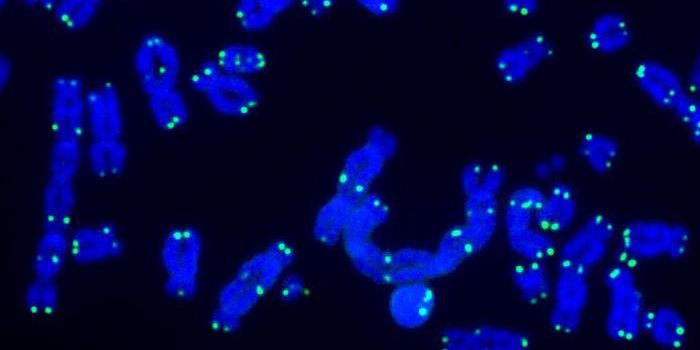

JUN 20, 2024Genetics & GenomicsOur genome is organized into chromosomes, which are shaped like little X's. Every time a cell divides, the genome ha ...